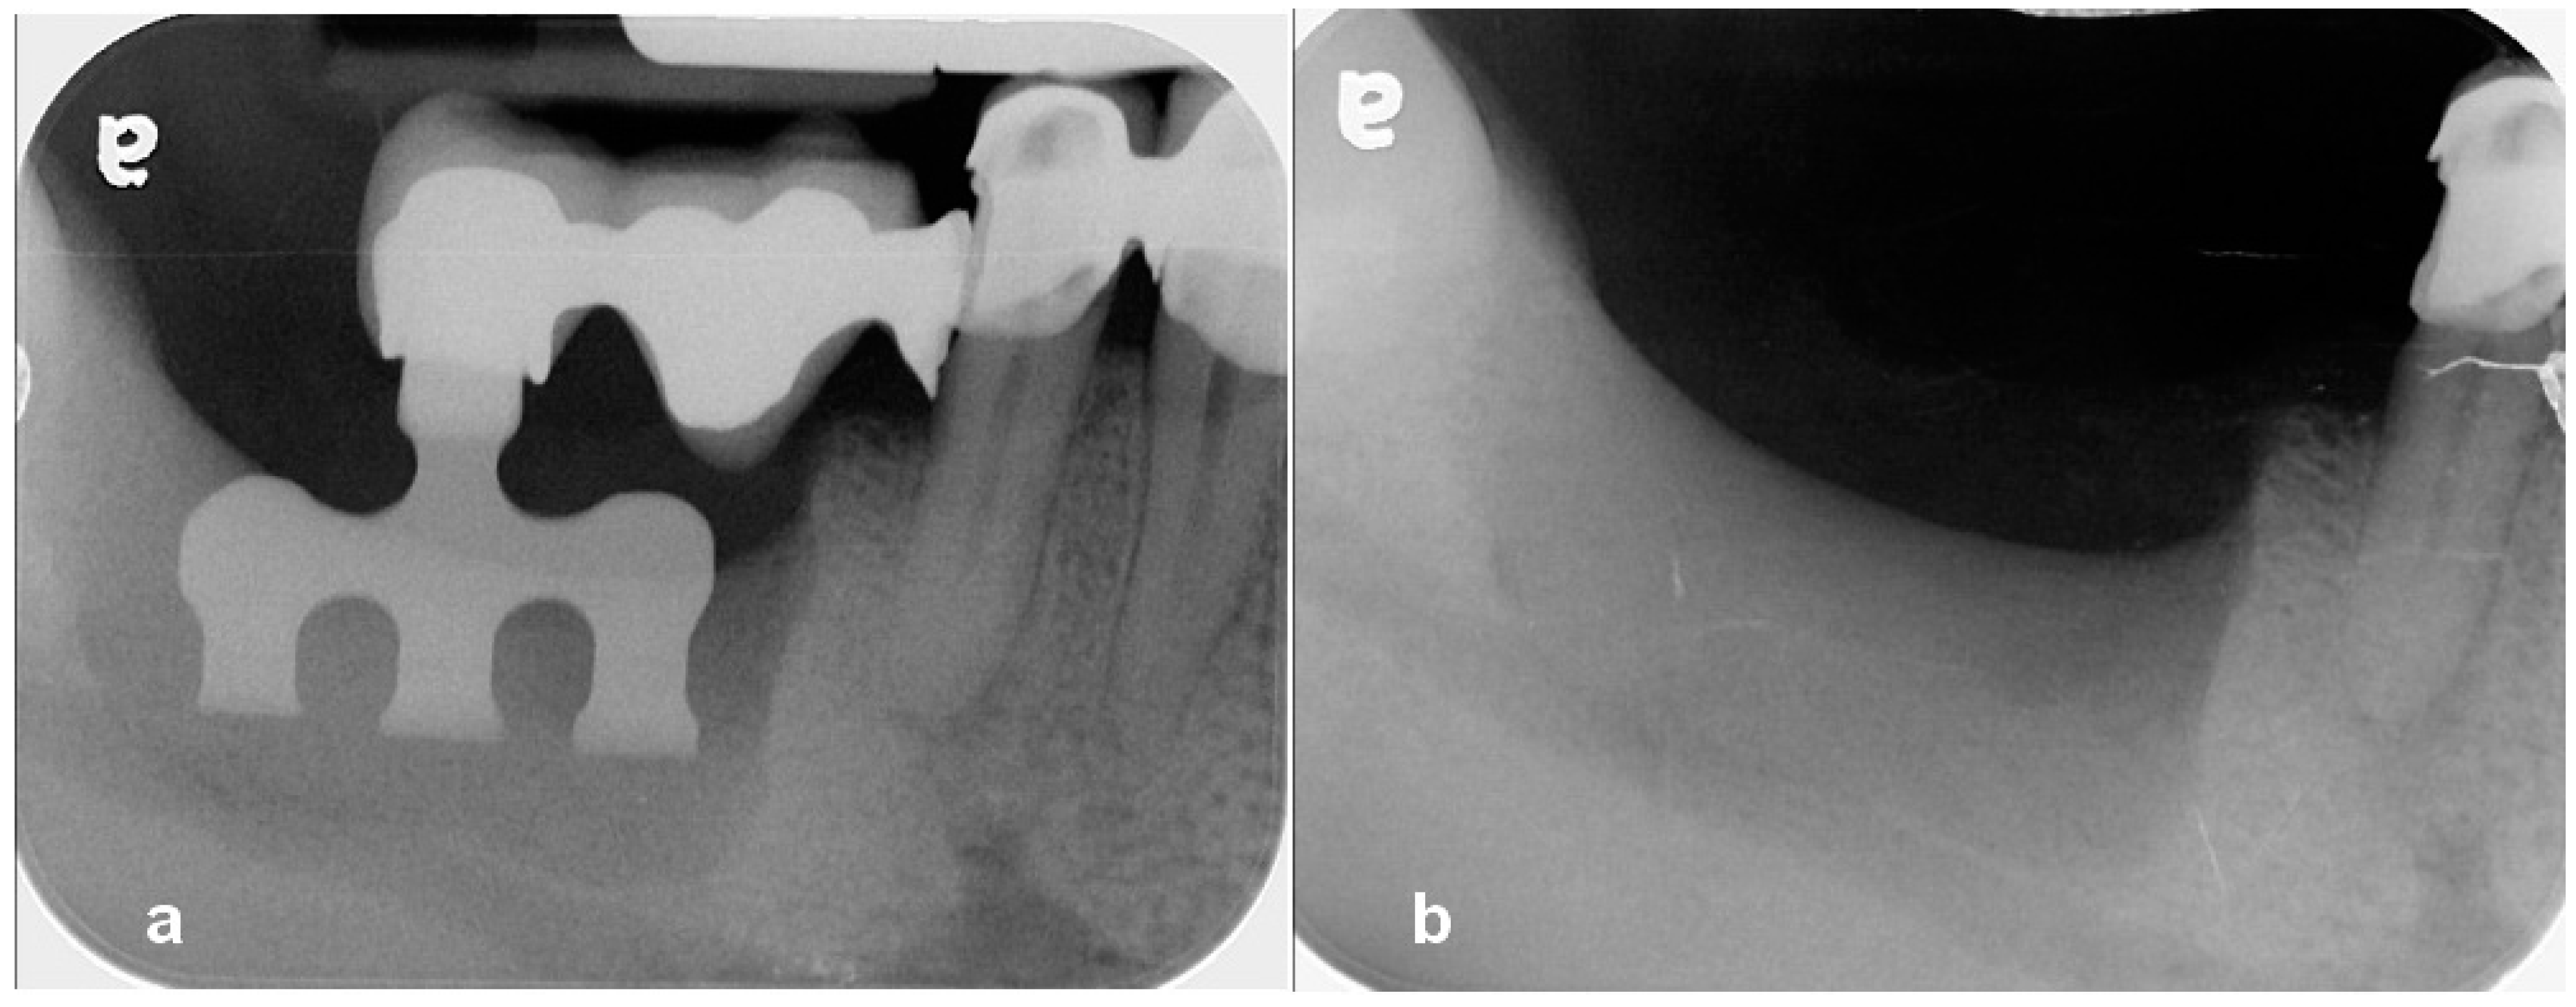

Utilization of Tenting Pole Abutments for the Reconstruction of Severely Resorbed Alveolar Bone: Technical Considerations and Case Series Reports

2. Case Presentations